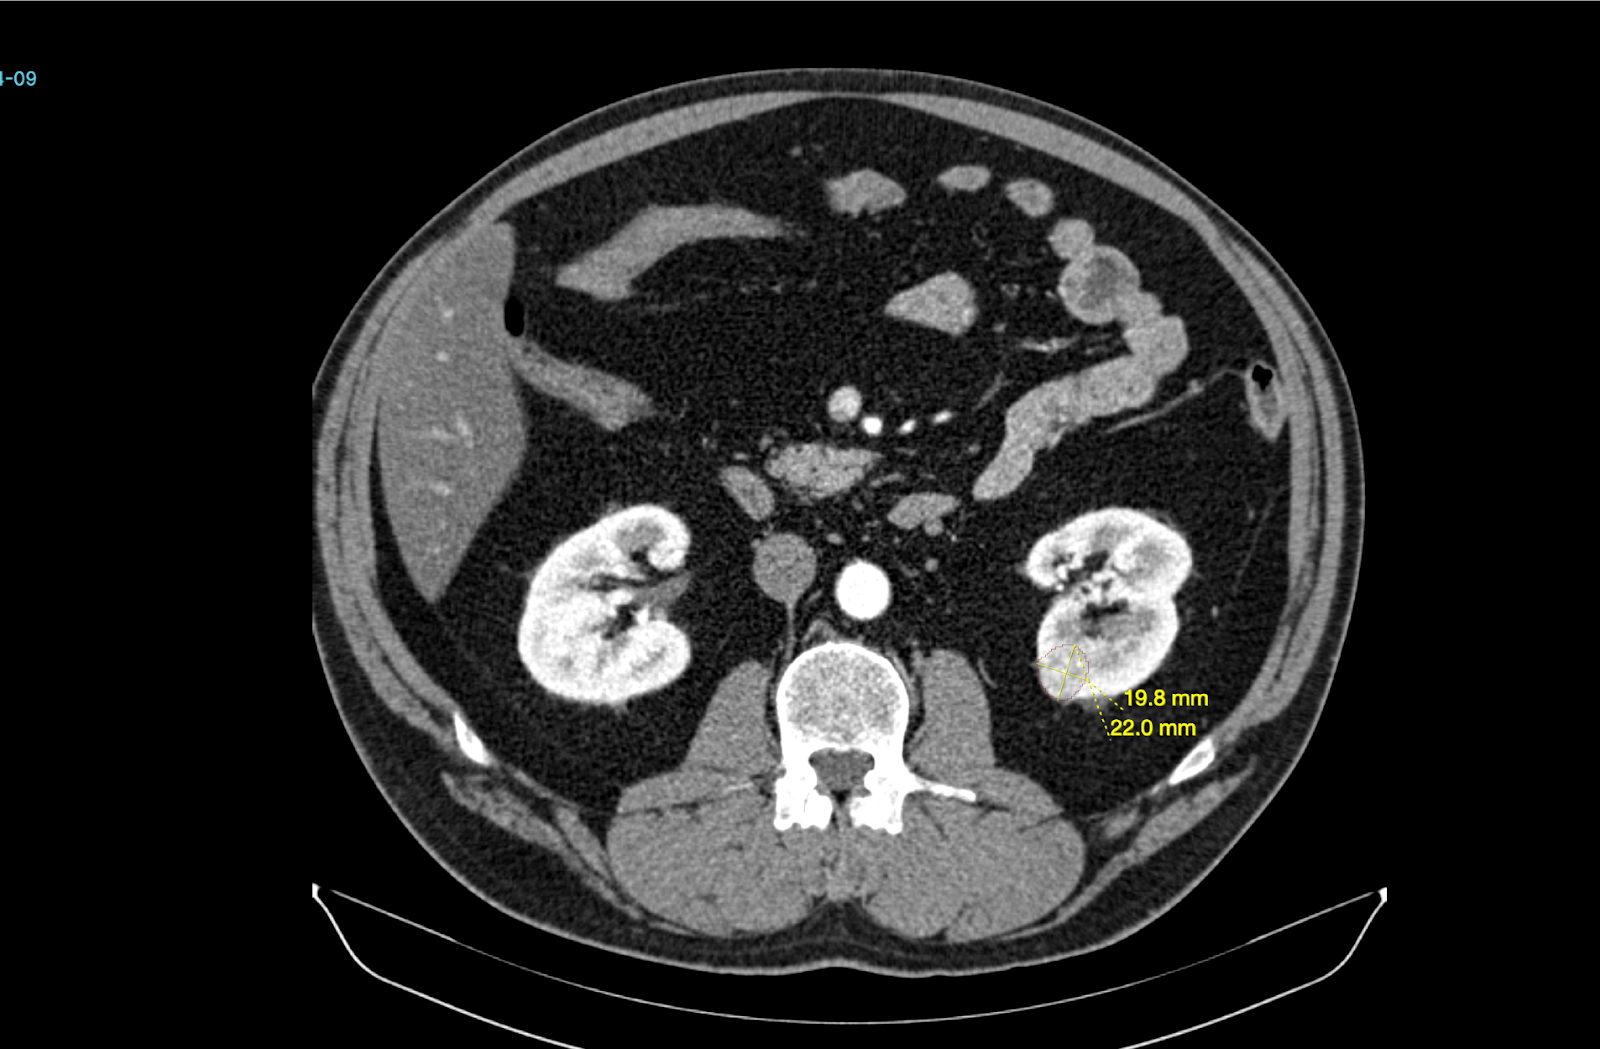

Better Medicine provides an AI-powered radiology solution, BMVision Kidney, designed to enhance diagnostic consistency and speed in kidney cancer detection. It is the first and only CE-certified AI model specifically trained to identify renal tumours from CT scans.

The software runs fully on-premise within UMC’s infrastructure, integrates with existing PACS and viewer systems, and processes CT data in standard formats to deliver interpretable results. Using advanced deep learning, BMVision Kidney automatically detects, segments, and characterises kidney lesions—including incidental findings—with accuracy comparable to radiologists. The solution strengthens diagnostic reliability, reduces variability, and supports faster, more consistent clinical decision-making within UMC’s radiology workflow.